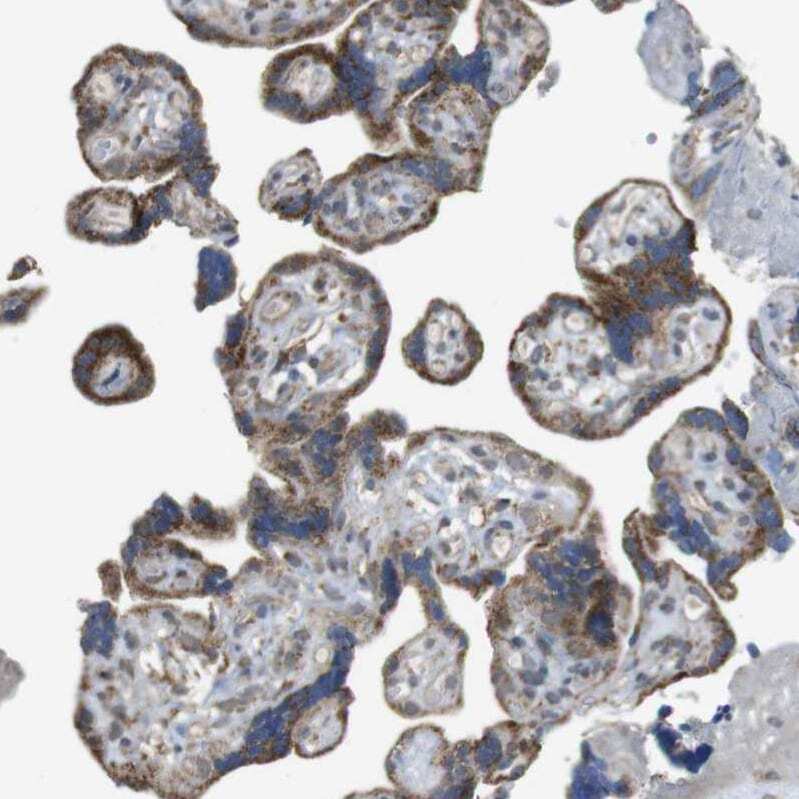

- Immunohistochemical analysis of CALHM2 in human placenta using CALHM2 Polyclonal Antibody (Product # PA5-53219) shows strong cytoplasmic positivity in trophoblastic cells.